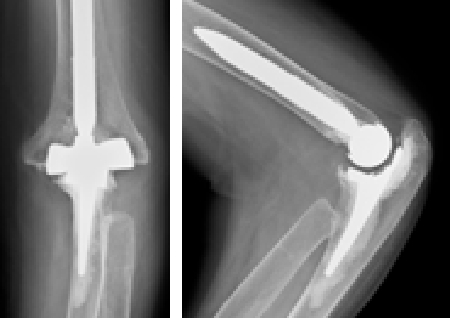

人工関節置換術

関節リウマチや変形性関節症の患者さんで、関節が破壊され機能が失われた症例に対し各関節(指、肘、肩)の人工関節置換術を行ない、関節機能の再建を行っています。

術前

左肘関節の変形を認めます

術後

人工関節して痛みや可動域が改善しました